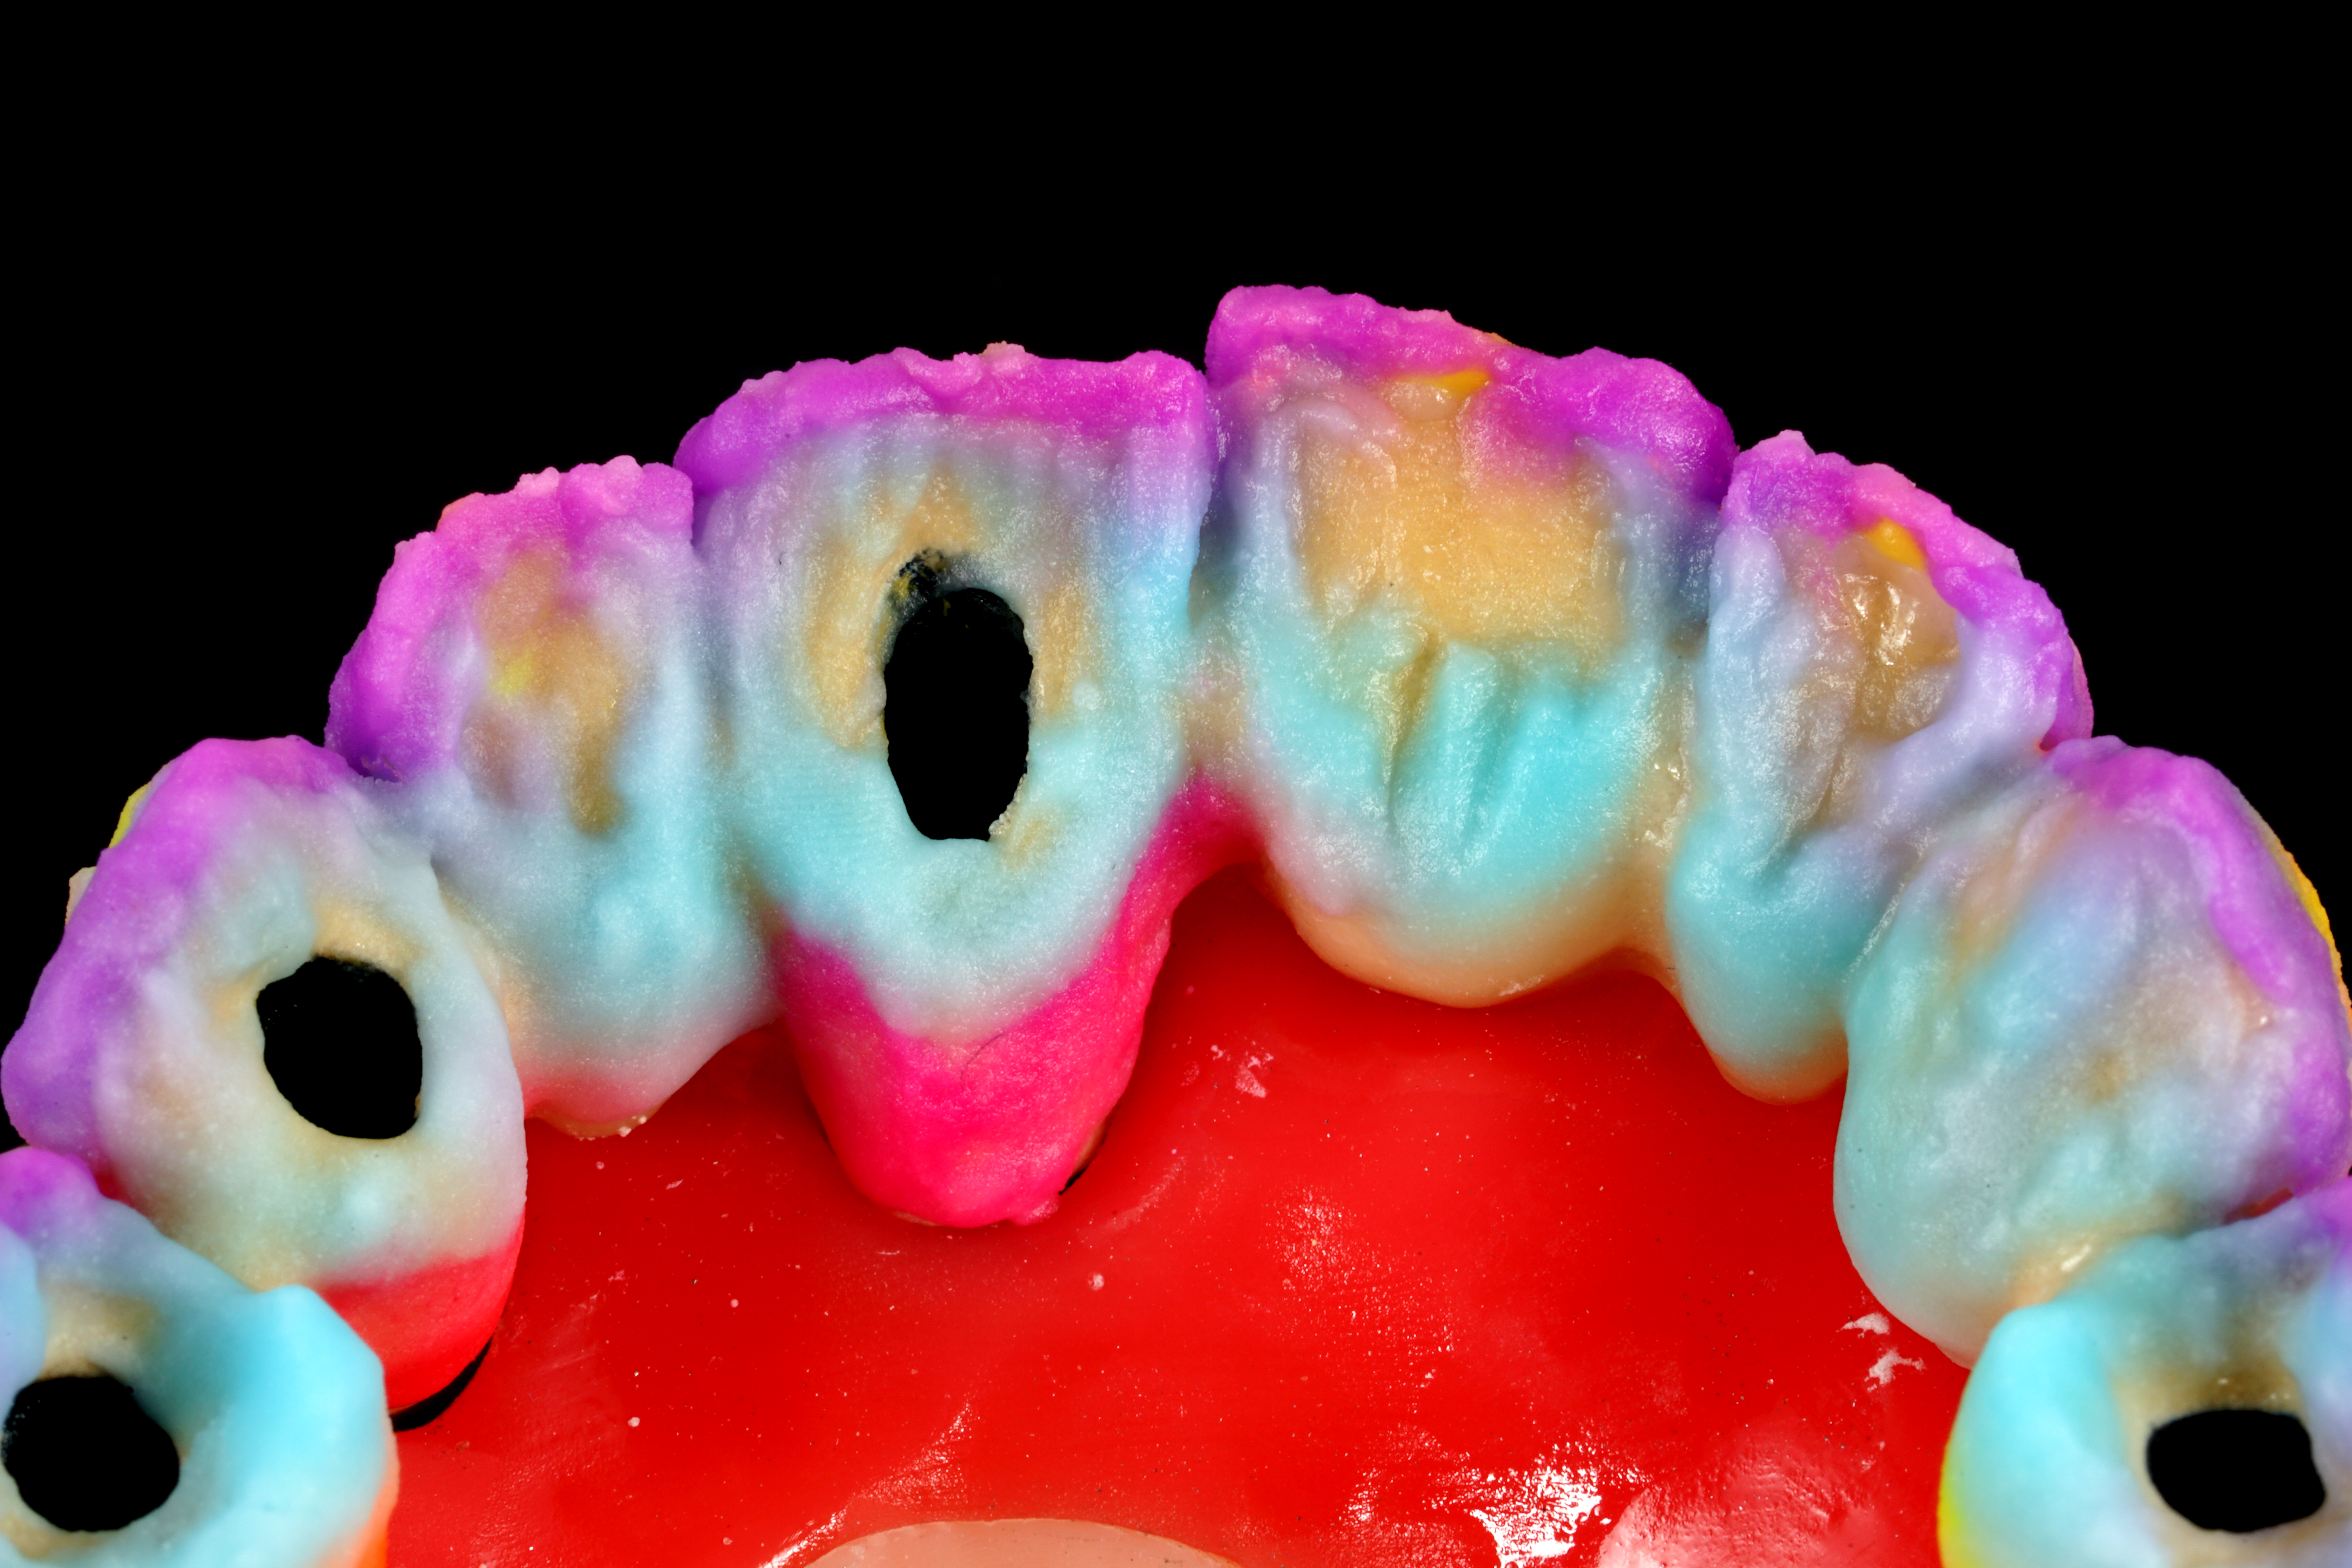

La parte di ceramizzazione è stata affidata ad una solida certezza interna al nostro laboratorio DentOne: Fabrizio Pasini, il quale ha espresso il suo sublime gusto estetico stratificando ad arte una base in CoCr con ceramica Shofu (Fig. 17, 18, 19, 20, 21).

Fig. 17. Stratificazione estetica multi-massa effettuata da Fabrizio Pasini

Fig. 18. Vista palatina della ceramizzazione del gruppo frontale e degli accessi vite con foro inclinato